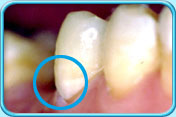

图中所见是蛀坏的牙齿补牙前的外貌。补牙前

图中所见是蛀坏的牙齿以汞合金填补后的外貌。补牙后